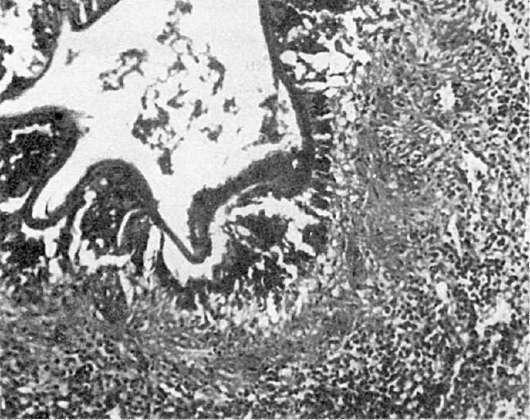

росту злокачественного новообразования. Выделяющиеся из пузырьков токсические вещества вызывают в окружающих тканях некроз и продуктивную реакцию. В грануляционной ткани много эозинофилов и гигантских клеток инородных тел, фагоцитирующих оболочки погибших пузырьков (рис. 289).

Рис.

289. Альвеококкоз. Среди некротических масс - пузыри эхинококка, окруженные зоной продуктивного воспаления